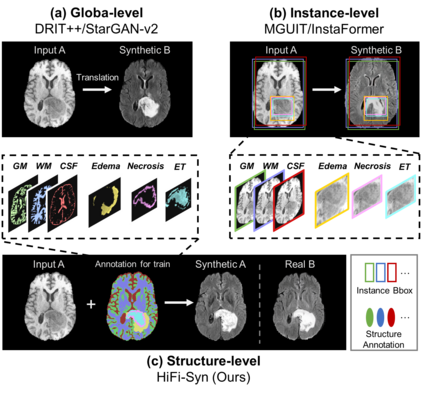

Synthesizing medical images while preserving their structural information is crucial in medical research. In such scenarios, the preservation of anatomical content becomes especially important. Although recent advances have been made by incorporating instance-level information to guide translation, these methods overlook the spatial coherence of structural-level representation and the anatomical invariance of content during translation. To address these issues, we introduce hierarchical granularity discrimination, which exploits various levels of semantic information present in medical images. Our strategy utilizes three levels of discrimination granularity: pixel-level discrimination using a Brain Memory Bank, structure-level discrimination on each brain structure with a re-weighting strategy to focus on hard samples, and global-level discrimination to ensure anatomical consistency during translation. The image translation performance of our strategy has been evaluated on three independent datasets (UK Biobank, IXI, and BraTS 2018), and it has outperformed state-of-the-art algorithms. Particularly, our model excels not only in synthesizing normal structures but also in handling abnormal (pathological) structures, such as brain tumors, despite the variations in contrast observed across different imaging modalities due to their pathological characteristics. The diagnostic value of synthesized MR images containing brain tumors has been evaluated by radiologists. This indicates that our model may offer an alternative solution in scenarios where specific MR modalities of patients are unavailable. Extensive experiments further demonstrate the versatility of our method, providing unique insights into medical image translation.